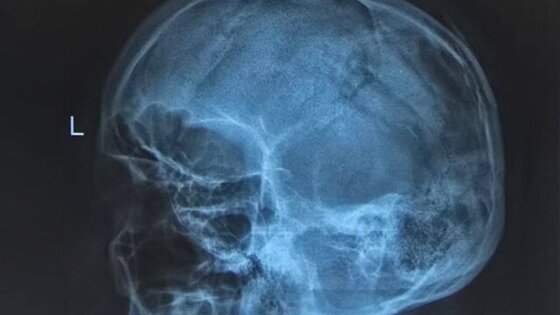

Травму мужчина получил на острове Попова. В связи с этим его экстренно перевезли на катере во Владивосток. Когда мужчину доставили в больницу, врачи выявили у него рубленые раны головы, оскольчатые и вдавленные переломы теменных костей, травматическое субарахноидальное кровоизлияние и ушиб головного мозга.

Пациенту требовалась срочная операция, так как из-за сильной кровопотери мужчина впал в геморрагический шок. Медики во время хирургического вмешательства обработали раны, удалили вдавленные фрагменты костей черепа, а также остановили кровотечение из поврежденных сосудов. В течение нескольких часов хирургам удалось собрать череп пострадавшего по частям.